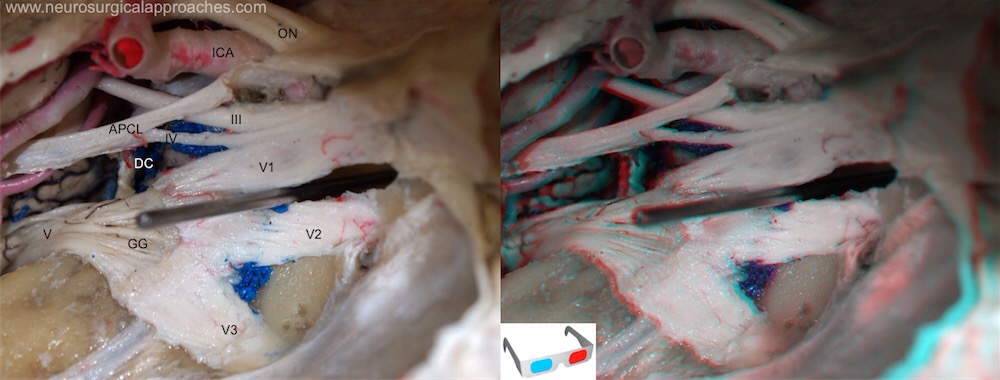

As duas raízes do V par têm origem aparente na face anterior (ântero-lateral) da ponte, no nível da união do terços inferiores e no limite com os pedúnculos cerebelares médios.

Depois de sair da ponte, atravessa a fossa cerebral posterior e tem de atravessar um canal na dura mater entrando depois numa cavidade designada por cavidade do trigémio também conhecida como fossa de Meckle.

Neste ponto as tensões meningeas como por exemplo compressões da SEB ou torções craniais, que coloquem muita tensão na tenda do cerebelo, podem perturbar o nervo nesta passagem e neste caso teremos sintomas que manifestem a sua compressão antes da sua divisão nos 3 nervos. Desta forma teremos sintomas em toda a face e não apenas na região correpondente a cada raiz. Também neste caso podem existir alterações do tónus dos músculos mastigadores.

Nesta fossa de meckel encontraremos o Gânglio do trigémio ( também conhecido como gânglio de gasser), local de sinapse do nervo trigémio antes da sua divisão nas 3 raizes.

Esta fossa de meckel está situado por cima da região petrosa do osso temporal, por isso perturbações neste osso (sobretudo as de rotação) podem provocar pressão neste gânglio e originar sintomas do trigémio. Um exemplo clássico é uma alteração na articulação ATM, que altere a posição do osso temporal, com consequente sintomatológia do nervo trigémio.